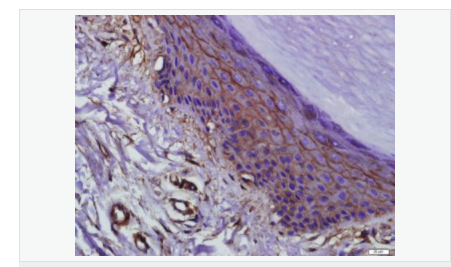

| 產(chǎn)品應(yīng)用 | WB=1:500-2000 ELISA=1:5000-10000 IHC-P=1:100-500 IHC-F=1:100-500 Flow-Cyt=1μg/Test ICC=1:100 IF=1:100-500 (石蠟切片需做抗原修復(fù)) not yet tested in other applications. optimal dilutions/concentrations should be determined by the end user. |

| 細(xì)胞定位 | 細(xì)胞膜 |

| 產(chǎn)品介紹 | This gene encodes an integral membrane protein which is located at tight junctions. This protein may be involved in the formation and maintenance of the tight junction. The possibility of several alternatively spliced products has been suggested but the full nature of these products has not been described. [provided by RefSeq]. Function: May play a role in the formation and regulation of the tight junction (TJ) paracellular permeability barrier. Subunit: Interacts with TJP1/ZO1 and with VAPA. Subcellular Location: Membrane; Multi-pass membrane protein. Cell junction, tight junction. Tissue Specificity: Localized at tight junctions of both epithelial and endothelial cells. Highly expressed in kidney. Not detected in testis. Post-translational modifications: Phosphorylated upon DNA damage, probably by ATM or ATR. Dephosphorylated by PTPRJ. May be phosphorylated by PKC during translocation to cell-cell contacts. Similarity: Belongs to the ELL/occludin family. Contains 1 MARVEL domain. SWISS: Q16625 Gene ID: 100506658 Database links: Entrez Gene: 18260 Mouse Entrez Gene: 100506658 Human Omim: 602876 Human SwissProt: Q16625 Human SwissProt: Q61146 Mouse Unigene: 592605 Human Unigene: 4807 Mouse Unigene: 31429 Rat Important Note: This product as supplied is intended for research use only, not for use in human, therapeutic or diagnostic applications. |